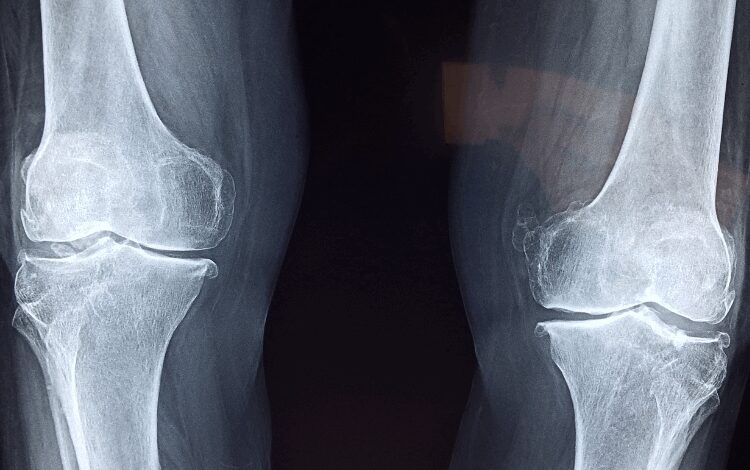

Get to the root with a chiropractor

A holistic approach means addressing your health concerns through more than medical treatments alone, and one that has become more popular and widespread as of late is the chiropractic approach. With the help of a primary care physician specialising in chiropractors, you may be able to address some of the root causes of physical pain, such as misalignment or inflammation. This approach has been found by many to be able to tackle the sources of issues such as joint pain, poor circulation, migraines, and more. It can also offer long-term relief to pain without the need for medication, which can help some people wean themselves off of medicine that they have a risk of becoming dependent on. You can search for chiropractors online. Check out websites such as this one from Dr. John Heary and compare services.